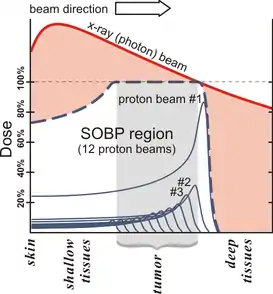

Protons can focus energy delivery to fit the tumor shape, delivering only low-dose radiation to surrounding tissue. As a result, the patient has fewer side effects. All protons of a given energy have a certain penetration range; very few protons penetrate beyond that distance.[9] Also, the dose delivered to tissue is maximized only over the last few millimeters of the particle's range; this maximum is called the spread out Bragg peak, often called the SOBP (see visual).[10]

To treat tumors at greater depth, one needs a beam with higher energy, typically given in MeV (mega electron volts). Accelerators used for proton therapy typically produce protons with energies of 70 to 250 MeV. Adjusting proton energy during the treatment maximizes the cell damage within the tumor. Tissue closer to the surface of the body than the tumor gets less radiation, and thus less damage. Tissues deeper in the body get very few protons, so the dose becomes immeasurably small.[9]

In most treatments, protons of different energies with Bragg peaks at different depths are applied to treat the entire tumor. These Bragg peaks are shown as thin blue lines in the figure in this section. It is important to understand that, while tissues behind (or deeper than) the tumor get almost no radiation, the tissues in front of (shallower than) the tumor get radiation dosage based on the SOBP.

The figure at the right of the page shows how beams of X-rays (IMRT; left frame) and beams of protons (right frame), of different energies, penetrate human tissue. A tumor with a sizable thickness is covered by the IMRT spread out Bragg peak (SOBP) shown as the red lined distribution in the figure. The SOBP is an overlap of several pristine Bragg peaks (blue lines) at staggered depths.

Megavoltage X-ray therapy has less "skin sparing potential" than proton therapy: X-ray radiation at the skin, and at very small depths, is lower than for proton therapy. One study estimates that passively scattered proton fields have a slightly higher entrance dose at the skin (~75%) compared to therapeutic megavoltage (MeV) photon beams (~60%).[3] X-ray radiation dose falls off gradually, needlessly harming tissue deeper in the body and damaging the skin and surface tissue opposite the beam entrance. The differences between the two methods depends on:

- Width of the SOBP

- Depth of the tumor

- Number of beams that treat the tumor

The X-ray advantage of less harm to skin at the entrance is partially counteracted by harm to skin at exit point.

Since X-ray treatments are usually done with multiple exposures from opposite sides, each section of skin is exposed to both entering and exiting X-rays. In proton therapy, skin exposure at the entrance point is higher, but tissues on the opposite side of the body to the tumor get no radiation. Thus, X-ray therapy causes slightly less damage to skin and surface tissues, and proton therapy causes less damage to deeper tissues in front of and beyond the target.[5]